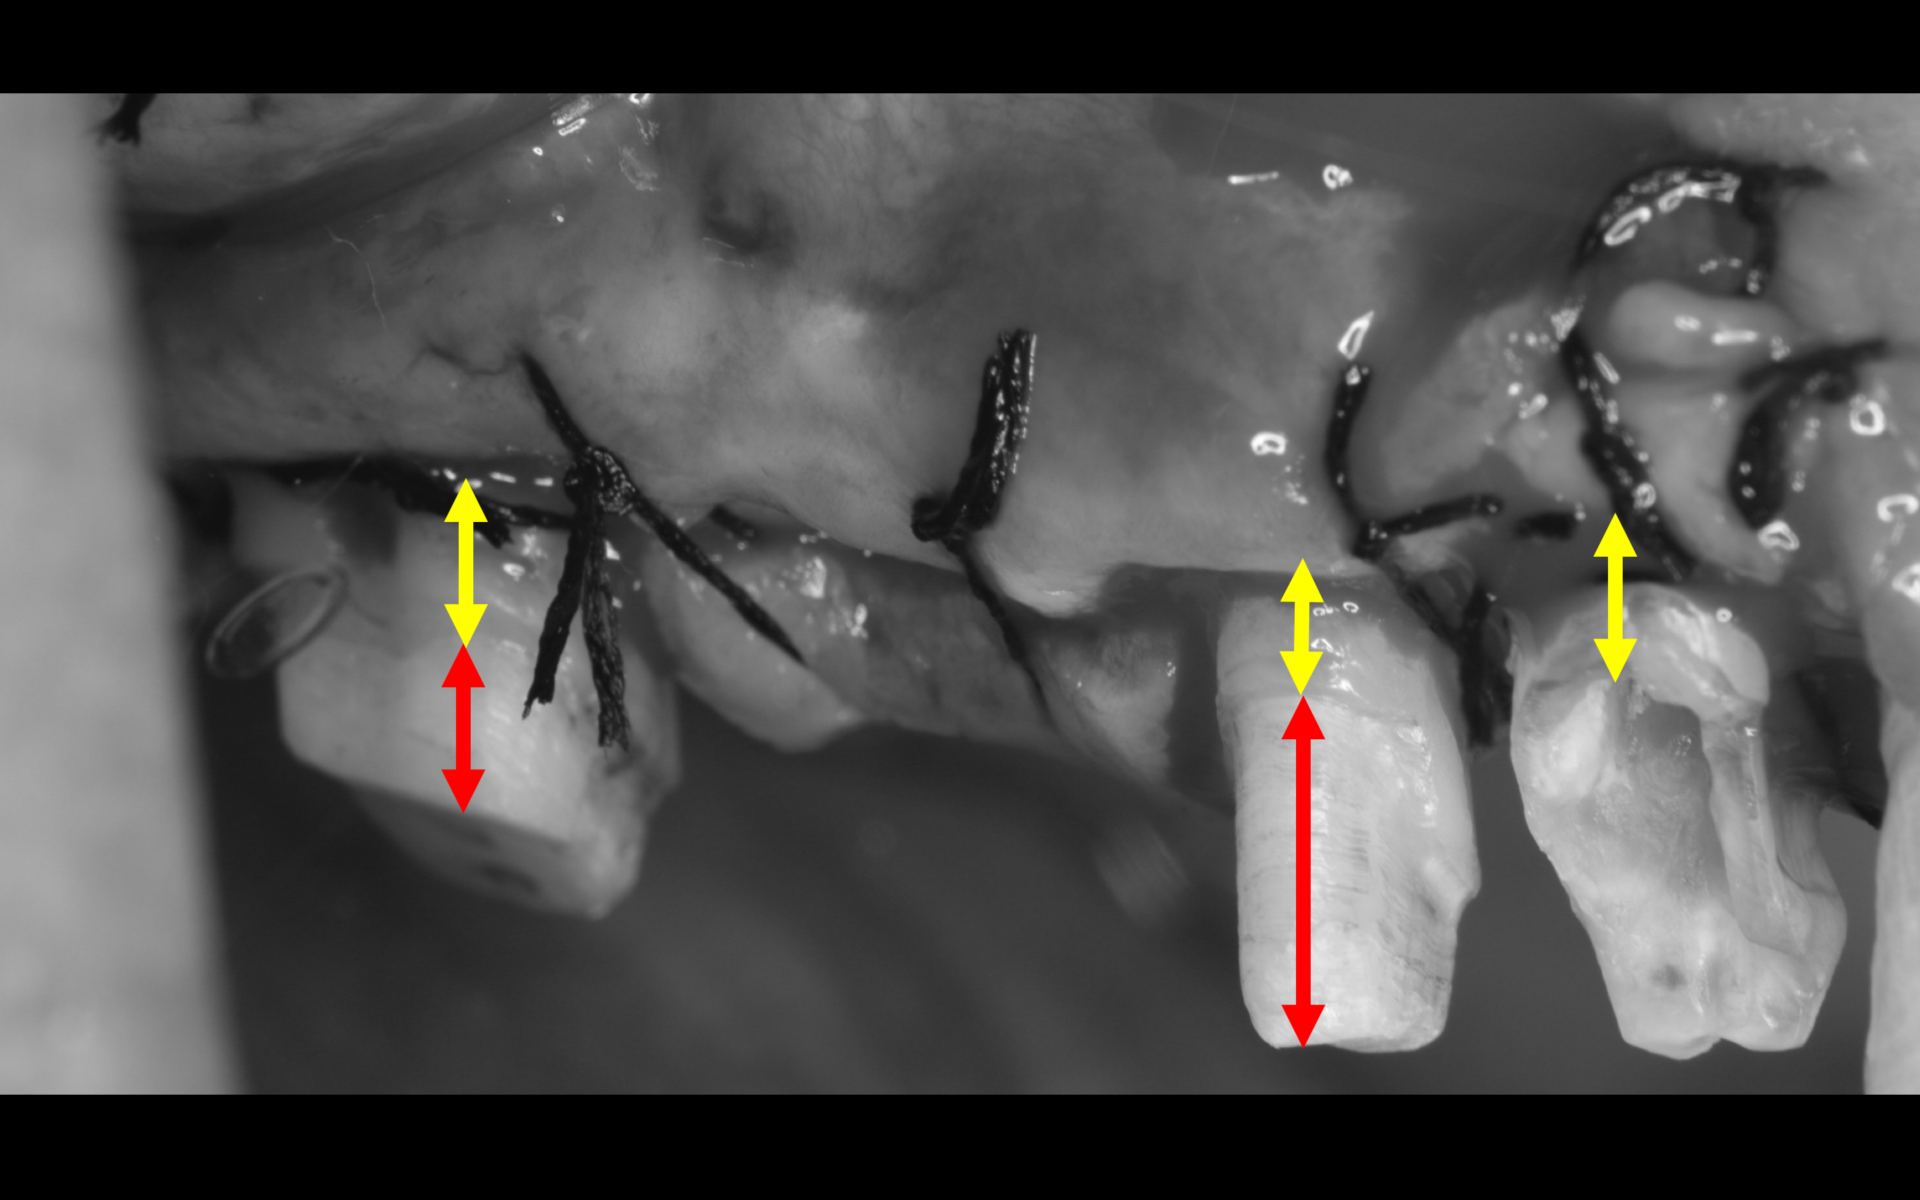

第二小臼歯に加え、第二大臼歯、第一小臼歯の3歯の根管治療終了。歯周外科前の写真。初診時にあった歯肉の腫れが消失している。黄色の矢印で示している第一、二小臼歯のように歯肉より深いところまで虫歯が進行してしまった場合(歯肉縁下カリエス)、歯を抜歯せずに保存するため、歯肉に埋まっている歯を表に出す手術(根尖側移動術)が必要となります。赤い矢印部分は歯が残っているように見えて、実はコンポジットレジンという白い材料ですので、歯ではありません。

術中の写真。歯肉の中に埋まっていた歯を表に露出させた状態。赤い矢印がコンポジットレジン、黄色の矢印が表に出た歯となります。歯の縁を表に出した状態で補綴(被せ物)することは根管治療の予後にも影響します。